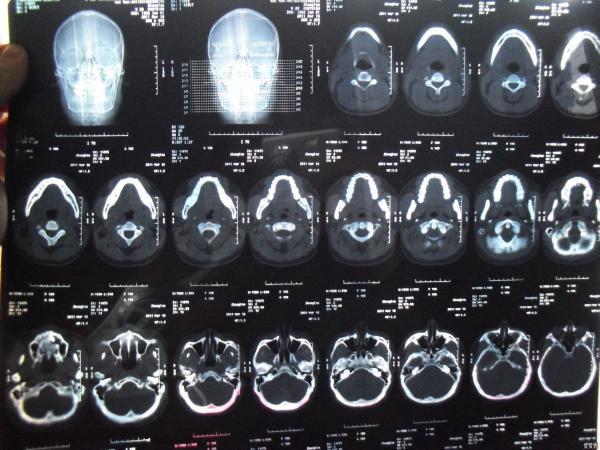

阻生牙下颌骨囊肿xct片请教如何处理

图片尺寸4000x4000